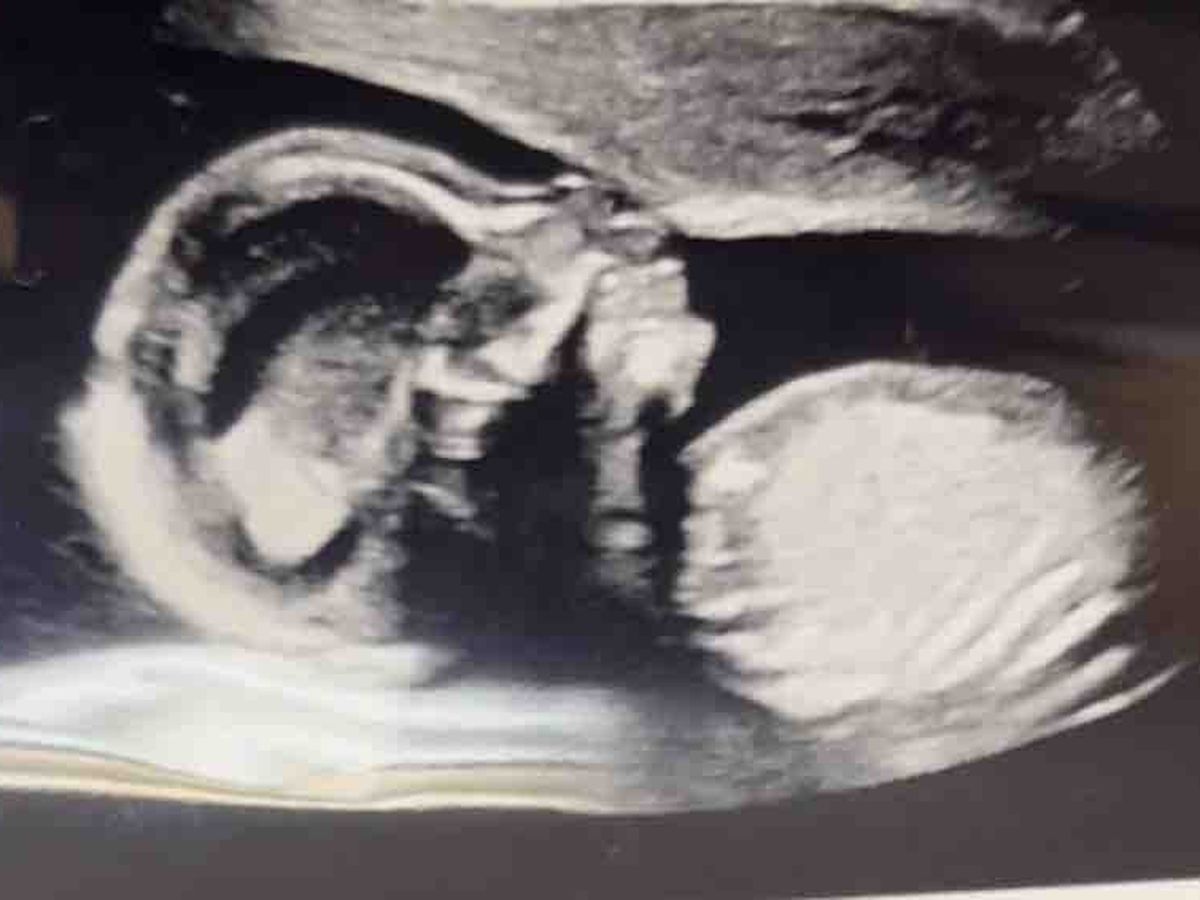

Hello my name is Kenoldrea. I am 25 years old and currently 7 months pregnant with my first child. I am fundraising to seek assistance while facing high risk pregnancy due to preeclampsia and placenta previa. It caught me off guard because I’ve always been an active and healthy person. I’m terrified. I am currently on emergency bed rest with the inability to work. Being that I am out of work I cannot save, afford food, medication that isn’t covered by my insurance, house essentials nor pay my bills. The hardest thing for me to do was reach out and ask for help. I have always done everything I can to ensure that I bring this bundle of joy into this world with ease and happiness. I have no one to turn to and I’m reaching out to you, whomever may see this. Please help me. Anything helps. Thank you.